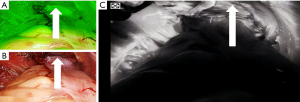

The patient was placed in the Trendelenburg position, with the head lower than the horizontal plane and the feet higher than the head. The right side was tilted slightly lower than the left side. The positioning of surgical team during the operation was as follows: the chief surgeon stands on the right side of the patient with a mirror support hand, and the assistant stands on the left side. A traditional five-port technique was used: first, a 10-mm trocar was placed at the upper edge of the umbilicus to establish a pneumoperitoneum at 13 mmHg. A 30° laparoscopic lens was inserted through the trocar, ensuring avoidance of the deep inferior epigastric artery. A 12-mm trocar was placed two fingerbreadths from the right anterior superior iliac spine as the main operating port for the chief surgeon; a 5-mm trocar was placed at the intersection of the right midclavicular line and the umbilical horizontal line as an auxiliary operating port; another 5-mm trocar was placed at the intersection of the left rectus abdominis (lateral margin) and the umbilical horizontal line as the main operating port for the assistant; and finally, a third 5-mm trocar was placed at the outer one-third as an auxiliary operating port. Intraoperative exploration revealed no metastasis in the abdominal organs, and the tumor was located in the rectum, 3 cm above the peritoneal reflection. Before the operation, 0.2 mL of ICG (H20055881; Rui Du, Dandong, China) was injected into the subserosa at three points 1 cm from the tumor margin. During the operation, the injected fluorescent substance made the surrounding lymph nodes appear green under the fluorescent laparoscope, helping surgeons accurately locate the lymph nodes (Figure 2).

The operation involved a medial approach with an ultrasonic scalpel (Ulthera, Inc., Mesa, AZ, USA), with the sacral promontory serving as the entry point and the yellow–white junction line serving as a reference (Figure 3A). During the operation, fusion imaging and lymphatic fluorescence imaging techniques were combined to precisely track the location of mesenteric lymph nodes (Figure 3B). The sigmoid mesentery was incised from the caudal-to-cranial direction, and a loose space was exposed; that is, the fusion fascia space (Toldt’s space) between the left mesocolon and Gerota’s fascia. The assistant’s left intestinal forceps continued to pull the upper rectum ventrally, and the right grasping forceps held the inferior mesenteric artery (IMA) pedicle, maintaining tension cranially and ventrally. The chief surgeon carefully expanded Toldt’s space along the anatomical plane using a combination of blunt and sharp dissection until reaching the root of the IMA, which was then followed by dissection of the IMA 253 lymph nodes. Dissection was carried distally to the bifurcation of the left colic artery (ICA) from the IMA and proximally along the ICA for the dissection of the lymph nodes between the left colic vessels, IMA, and aortic angle (group 253). After lymph node dissection, the IMA was dissected distally and exposed up to the ICA, which was preserved. The superior rectal artery was transected, and the inferior mesenteric vein (IMV) was dissected at the same level as the arterial transection (Figure 4A). After vein transection, an ultrasonic scalpel was used for rapid and precise dissection to expand Toldt’s space, with special attention being paid to protecting the genital vessels, hypogastric plexus nerves (lumbar spinal nerves), and ureters (superior hypogastric plexus) (Figure 4B).